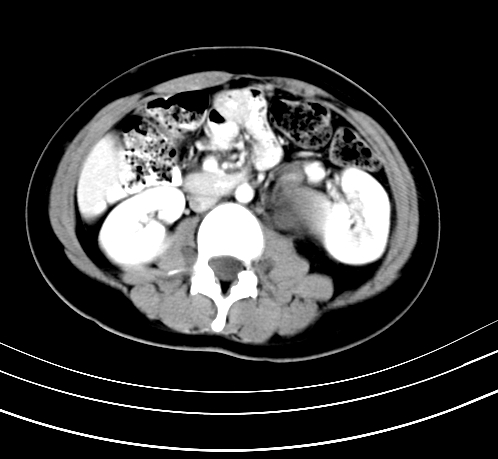

标题: CT23915:女 20岁 全身长疙瘩三年 今日多体位查 看看吧 [打印本页]

标题: CT23915:女 20岁 全身长疙瘩三年 今日多体位查 看看吧

腹部平扫

神经纤维瘤病

支持神经纤维瘤。